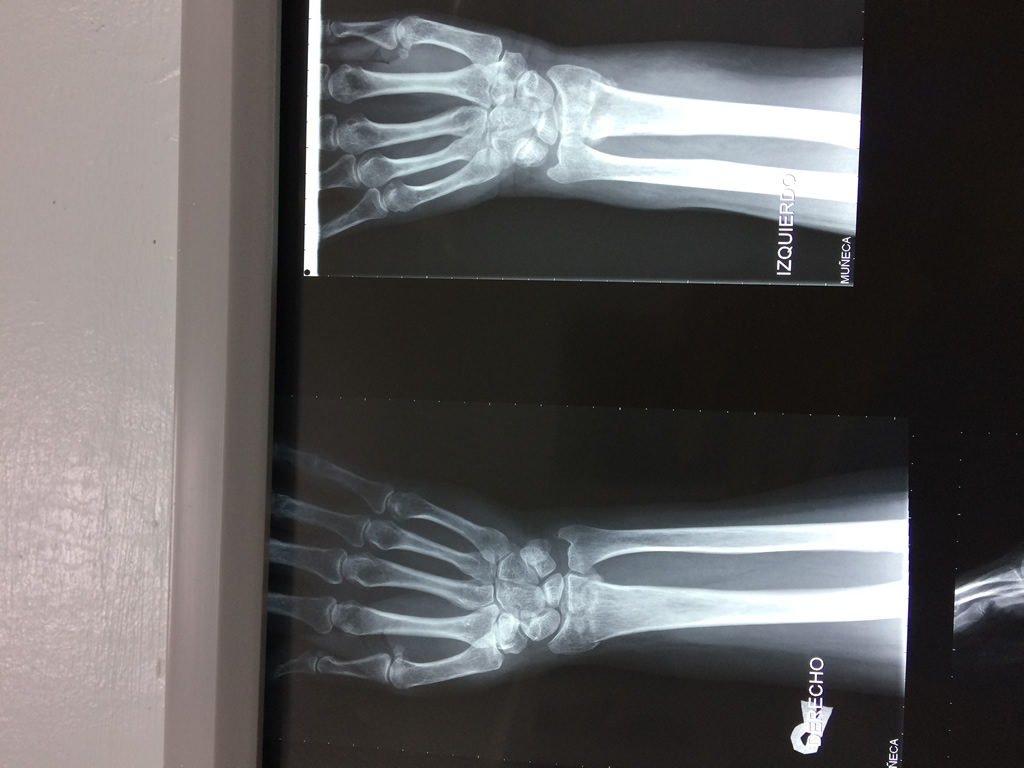

Cirugías de Muñecas

Los procedimientos más comunes en cirugía de la mano son aquellos destinados a reparar traumatismos, incluyendo lesiones de tendones, nervios, vasos sanguíneos, y articulaciones; huesos fracturados; y quemaduras, cortes, y otros daños de la piel.